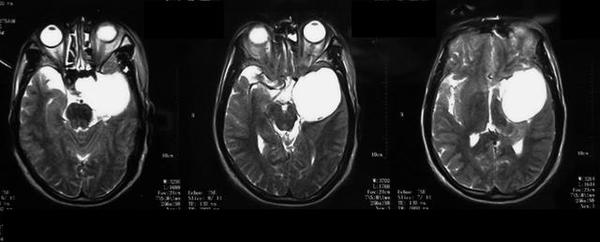

MRI表现:病灶中相对脑实质来说T WI上呈等信号,或稍低信号,信号均匀,少数内部见小片高信号。T WI及T 一FLAIR上均为明显高信号。CSHAs的血供丰富及解剖结构较复杂,术前误诊率和术后致残率均较高,掌握其CT、MR及DSA等各种影像学检查方面的特征性表现,可提高术前定位及定性诊断的准确率,对于临床治疗方案的制定、确定手术入路以及减少手术致残及致死率有着十分重要的意义。

有学者认为海绵窦海绵状血管瘤与雌激素、孕激素和促性腺激素的水平有关 。而Ohata等则认为这是颅内高血流状态和动脉收缩压升高所致。有文献报道部分患者有腺垂体功能减退的症状,与肿瘤向鞍内生长有关。海绵窦海绵状血管瘤的影像学特点为同时累及鞍旁和鞍内的单发大肿块,呈哑铃状,密度多均匀而少出血和钙化,其在CT扫描时呈等或稍高密度,瘤内常无钙化,可侵蚀颅骨,但一般不伴骨质增生。MRI扫描时T wI明显高信号和显著均质强化是其重要的诊断依据 ” 。